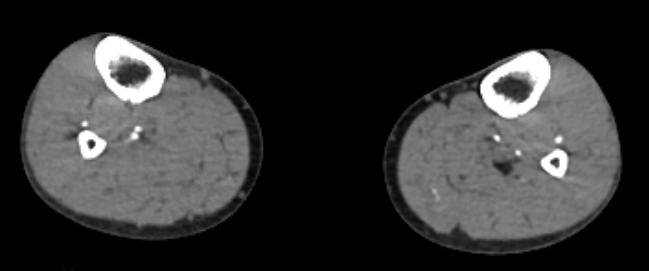

КТ сосудов (артерий) нижних конечностей (2 ноги)

от бифуркации аорты до коленного сустава

7 500 руб